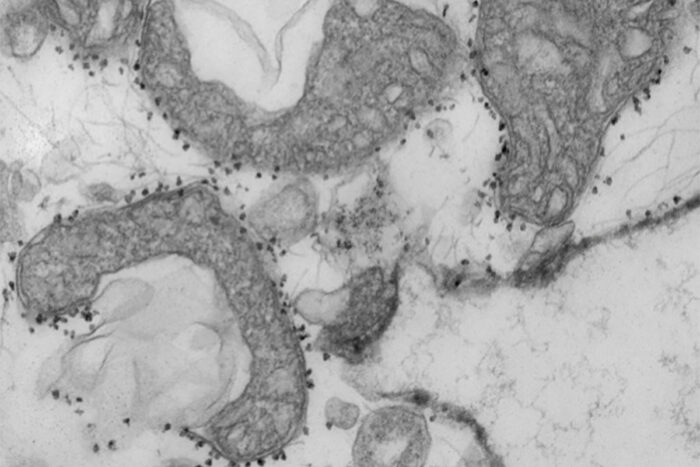

Dr. Hrishikesh Kulkarni has been published in JCI Insight. The article is titled “Rapid Blood Test Identifies COVID-19 Patients at High Risk of Severe Disease.” Dr. Kulkarni has received a news release at Washington University School of Medicine about his article as seen here.